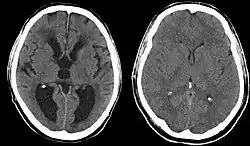

Ein Hydrocephalus (von griechisch ὕδωρ hydōr ‚Wasser‘, und κεφαλή kephalē ‚Kopf‘), auch Hydrozephalus geschrieben, ist eine krankhafte Erweiterung der mit Liquor gefüllten Flüssigkeitsräume (Hirnventrikel) des Gehirns. Er wird auch Wasserkopf oder veraltet Gehirnwassersucht und Hydrocephalie genannt.

- Hydrocephalus internus: Erweiterung nur der Hirnventrikel